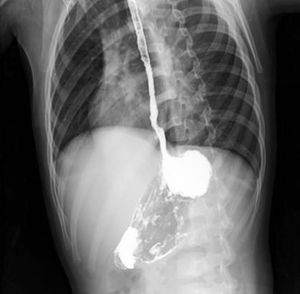

This occur due to acids or alkalies. Alkalies are odourless and tasteless so they are more likely to be ingested. The effects of alkalies are liquefaction, dehydration, and thrombosis of blood vessels and they usually lead to fibrous scarring. While Acids can cause coagulative necrosis with eschar formation. The best way to diagnose these conditions is by skilled early endoscope, deep ulcers and lesions will most likely perforate the wall of esophagus, but if there is only edema of the mucosa then eventually it will heal. The most important complication which is seen in this photography is stricture formation and it requires regular endoscopy to be assessed. Note that corresives such as sodium hydroxide or sulphuric acid are used for suiciding purpose, and accidental ingestion might be seen in children.